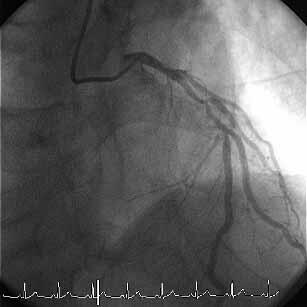

��̃P�[�X�i�ʐ^�P�C�Q�j�ŊF�Aproximal LCX total

occlusion

�Ƀ��C�A�͎h����܂���������܂���ł����B���C�A�͍ŏ���intermediate,

���ǁA��Ԗڂ̊��҂���͍���ŁALAD CTO ��RCA lesion�͉�

���ł����̂ł��̂܂ܑމ@�A��Ԗڂ̊��҂���� triple vessel

total occlusion, LV dysfunction (EF=20%)

�� CABG�ɂȂ�܂����B